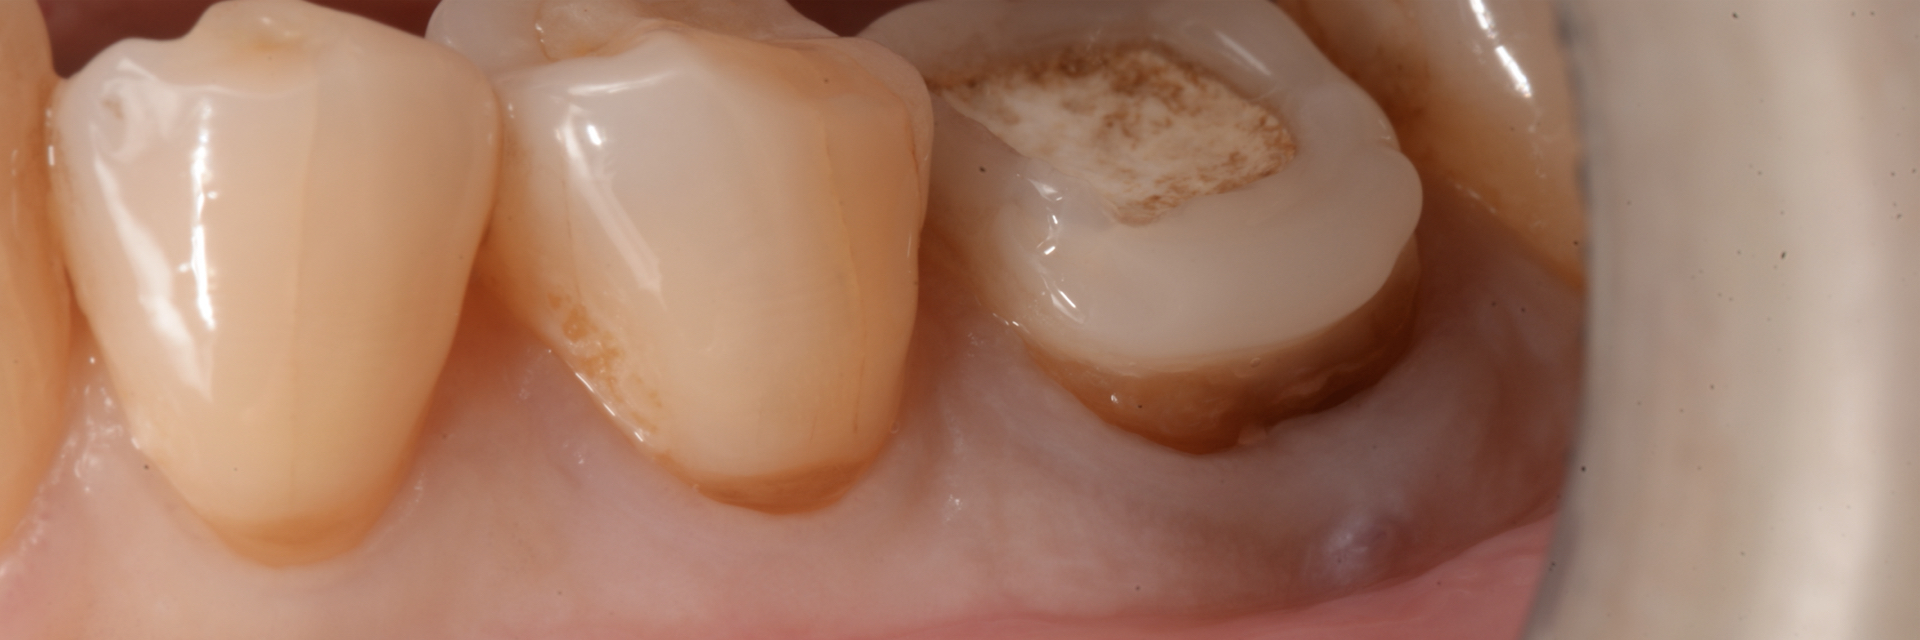

上唇の腫脹を認め、CT検査にて根尖部に嚢胞様透過像を認めた。左上の前歯が不自然に大きく噛み合わせが強くなっていたことがフレアアップの一因と考える。精密根管治療を行い、感染経路を遮断したのち歯根端切除術にて嚢胞を摘出した。

治療前